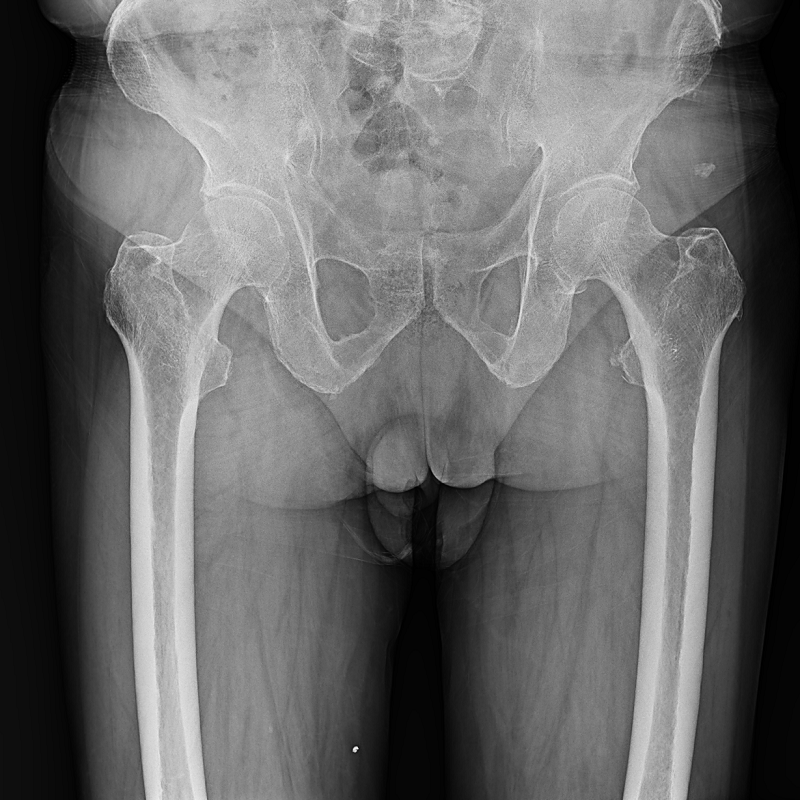

Clinical picture

臨床圖片